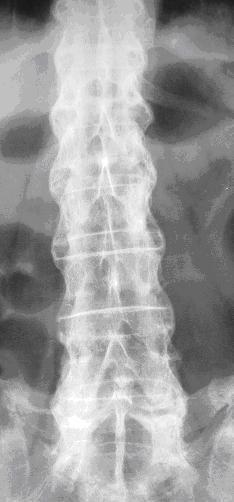

强直性脊柱炎治疗

主页 > 强直性脊柱炎治疗 >